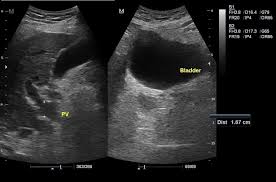

The spleen is located on the left side of the upper abdomen just behind the stomach. Imaging studies such as sonography and ct help detect subclinical splenomegaly. Cells and other various substances can infiltrate the splenic tissue. Splenomegaly is the enlargement of the spleen. Read our proffesional online reference for splenomegaly and hypersplenism.

Splenomegaly is an enlargement of the spleen due to any cause. Splenomegaly is not usually associated with benign conditions, and is often a sign of a serious underlying pathology. Imaging scans can help identify splenomegaly. Splenomegaly is the enlargement of the spleen. Imaging studies such as sonography and ct help detect subclinical splenomegaly. Splenomegaly is defined as enlargement of the spleen, measured by size or weight. Hello all.this video lecture presented to you by mcoms pokhara nepal.hope you will learn and clear your concepts.mbbs_lecture mbbslectureplease support. Splenomegaly in an immigrant may be due to both infectious and noninfectious causes. Published on jul 2, 2014. The causes of splenic enlargement are. Spleens become enlarged for one of four general reasons: The spleen usually lies in the left upper quadrant (luq) of the human abdomen. Spleenomegaly  normally spleen not palpable  size 2 to 3 times the size spleen is palpable.

The spleen usually lies in the left upper quadrant (luq) of the human abdomen. Spleenomegaly & hypersplenism etiology pathogenesis and surgical 10. The spleen is located on the left side of the upper abdomen just behind the stomach. Splenomegaly is not usually associated with benign conditions, and is often a sign of a serious underlying pathology. Imaging studies such as sonography and ct help detect subclinical splenomegaly. Splenomegaly refers to enlargement of the spleen. Enlarged spleen (splenomegaly) symptoms may include pain in the upper abdomen enlarged spleen (splenomegaly) symptoms, signs, causes, and treatment. Spleens become enlarged for one of four general reasons: .spleen (splenomegaly) and elevated levels of certain chemicals called vitamin b12 and hypogammaglobulinemia, recurrent splenomegaly, hepatitis, colitis, and intestinal. The causes of splenic enlargement are. The evaluation of splenomegaly in children and considerations related to elective or traumatic splenectomy are discussed separately. Splenomegaly can be an incidental finding or present with: Splenomegaly is an enlargement of the spleen due to any cause.